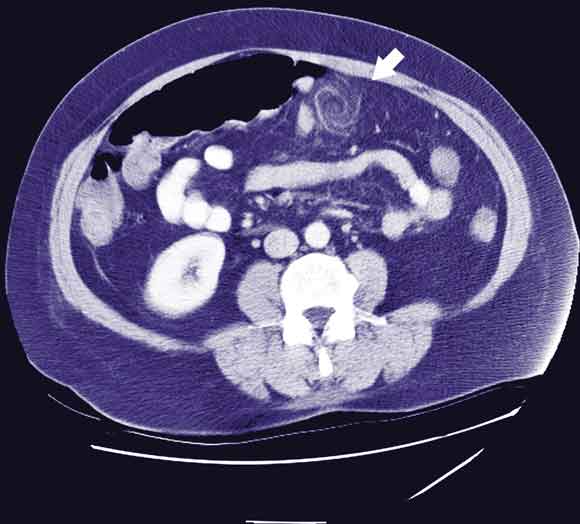

A 44-year-old woman presented with a 3-day history of worsening right upper quadrant pain associated with nausea, anorexia and fever. She had localised tenderness and guarding in the epigastrium. Initial ultrasound imaging showed a distended gallbladder containing calculi, without wall thickening. A computed tomography scan (performed because of increasing pain) showed a whorled structure in the anterior abdomen (Box 1). At laparotomy this was seen to be torsion of a segment of the greater omentum. Histology of the resected specimen showed congestion of the vessels, haemorrhagic infarction and focal fat necrosis (Box 2). She made an uncomplicated and rapid recovery.

Primary omental torsion is a rare cause of acute abdomen. It may affect children and adults, and is commonly misdiagnosed preoperatively as appendicitis. Some cases have presented as acute cholecystitis.1,2 Kimber et al identified 13 cases of omental torsion or infarction in about 8000 cases of suspected appendicitis over a 20-year period.3